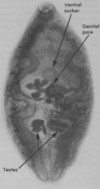

- Paragonimus kellicotti

- Lung fluke

- Canine and Feline

- crayfish

- Lungs

- Fecal float

- Yes; ingestion of intermediate host

- Leaf-shaped body, oral and ventral sucker, no anus

- none; coughing, dyspnea, pneumothorax

- Tetracyclines

- Paragonimus kellicotti

- Lung fluke

- Canine and Feline

- crayfish

- Lung

- Fecal float

- Yes; ingestion of intermediate host

- Operculum with shoulders, shell is thicker opposite to operculum

- None, coughing, dyspnea, pneumothorax

- Tetracycline